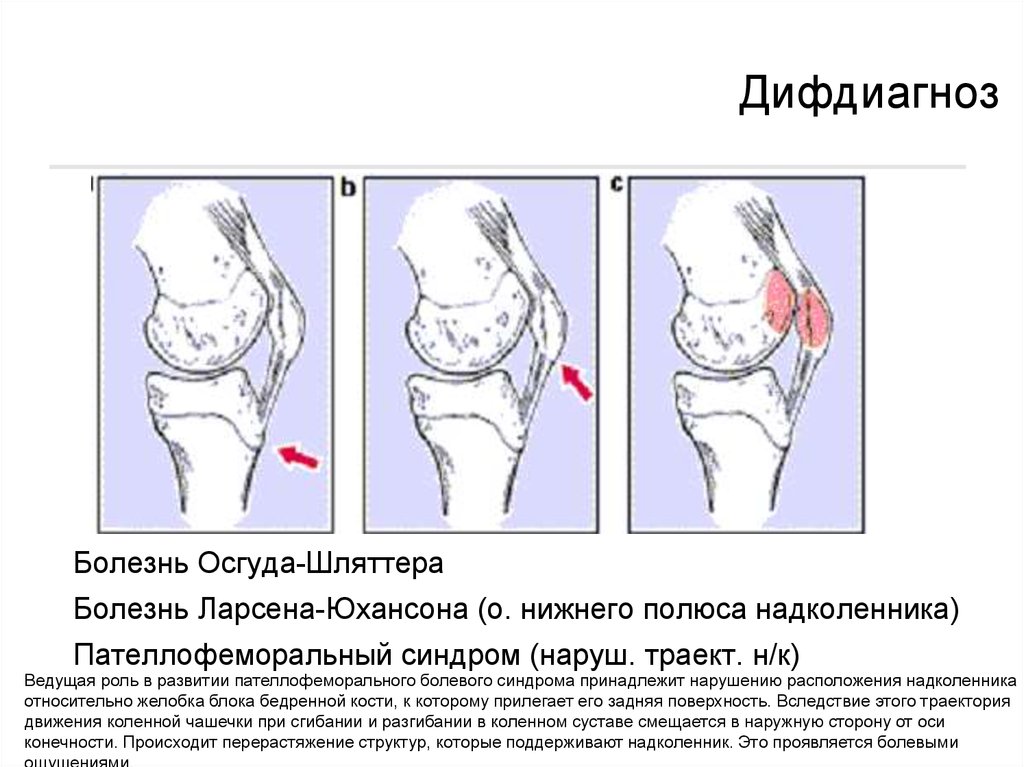

Ларсена йохансона

Ларсена йохансона 146 фото